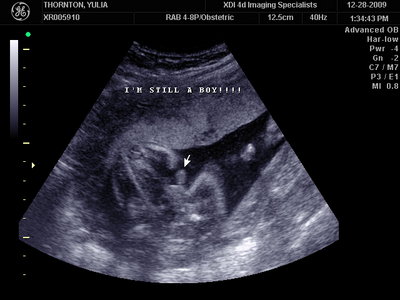

Ну ладно, тогда и я нашего писюна покажу  Надеюсь, Джеффри на меня не обидится Вот это в 23 недели: (там оборудование переключалось из режима 3Д в обычный 2Д)

| Вложения: |

MY BABY SONO!_2_15.JPG [ 112.35 КБ | Просмотров: 1241 ]

Sweetheart75 писал(а): Ну ладно, тогда и я нашего писюна покажу  Надеюсь, Джеффри на меня не обидится Вот это в 23 недели: (там оборудование переключалось из режима 3Д в обычный 2Д) Oоо, такое достоинство невозможно не заметить  А в 30 недель так вообще!